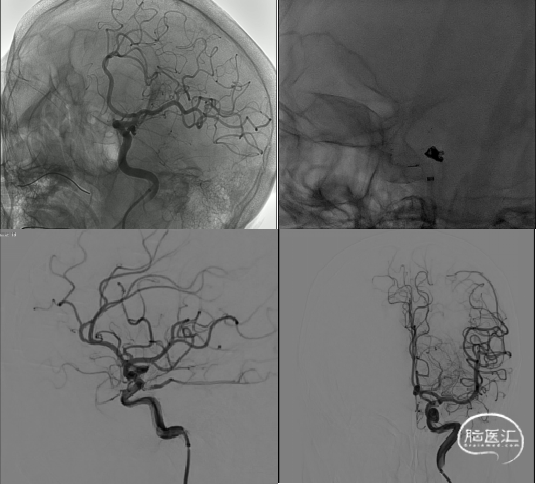

患者平卧位,双管喉罩全麻,术野常规消毒铺无菌巾,以Seldinger氏技术穿刺右股动脉置8F鞘,肝素盐水(5000U/500ML)持续滴注,导丝引导下送入5F脑造影导管依次行双侧颈总动脉、双侧椎动脉血管造影,超选择性左侧颈内动脉3D造影。

造影所见:双侧颈动脉血管稍迂曲僵硬,双侧后交通动脉开放,左侧颈内动脉后交通段可见一“囊状”突起,大小约6.19mm*4.07mm*2.35mm,瘤颈4.03mm,基底宽,边缘不光整,有两个子瘤,指向后下方,后交通动脉从瘤颈处发出。

造影

患者平卧位,双管喉罩全麻,术野常规消毒铺无菌巾,以Seldinger氏技术穿刺右股动脉置8F鞘,肝素盐水(5000U/500ML)持续滴注置入8F输送导管+6F远端通路导管,输送导管于左侧颈内动脉起始端,远端通路导管置于左侧颈内动脉海绵窦段,接驳Y阀,肝素盐水(5000U/500ML)持续滴注,手推造影剂,获得理想的工作角度,充分暴露动脉瘤瘤体、瘤颈、载瘤动脉、后交通动脉以及远端通路导管头端,通过在微导丝引导下用一根微导管置于左侧大脑中动脉内。

通过在微导丝引导下用一根微导管置于动脉瘤瘤体,选择一枚凤弹簧圈(AEC-2.5-06-S)由微导管置入瘤囊下方子瘤内,微导管(150cm*6cm)内送入支架(Neuroform Atlas 4.0mm*21mm),释放支架,支架头端位于左侧大脑中动脉M1段内,末端位于左侧颈内动脉眼段,支架展开贴壁满意,撤出微导管(150cm*6cm)。微导管内继续送入一枚凤弹簧圈(AEC-04-10-S)“成栏”,“成篮”满意,依次置入凤弹簧圈2枚(AEC-2.5-04-H,AEC-02-02-S)。

造影,确认致密填塞,载瘤动脉,后交通动脉,大脑前动脉、大脑中动脉未闭塞,脑供血正常。微导丝引导下从瘤囊撤出微导管,正侧位造影,未见血管闭塞。

回撤8F输送导管+6F远端通路导管造影,确认致密填塞,载瘤动脉,后交通动脉,大脑前动脉、大脑中动脉未闭塞,脑供血正常。拔出动脉鞘,压迫穿刺点,无菌包扎。